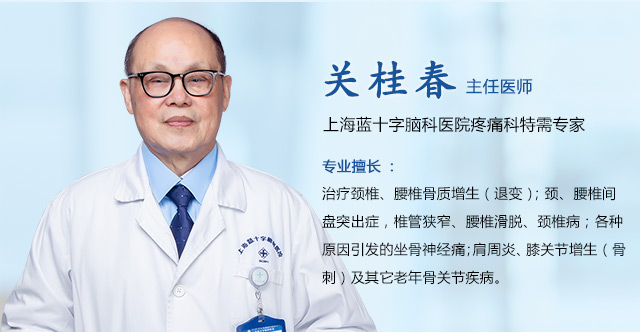

近日,上海蓝十字脑科医院收治了一位年近六旬的女性面肌痉挛患者。该患者5年前无明显诱因突然出现右侧颞部及耳后肌肉紧绷感,伴右侧眼部、面部不自主阵挛性抽搐。抽搐无法自我控制,尚不影响睡眠。

入院后,经面神经MRTA平扫+增强检查显示,患者右侧面神经与周围小血管关系密切。在对患者病情及影像学资料进行评估,并告知患者及家属手术风险后,上海蓝十字脑科医院神经外科主任沈建康教授团队为患者实施了面神经微血管减压手术。